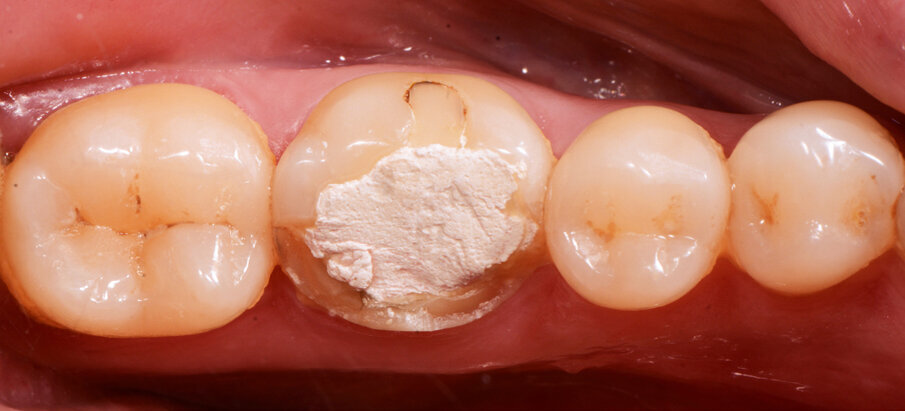

Fig. 4: Characterised and glazed crown.

A 45-year-old male patient presented to the practice with a restoration on tooth #46. The tooth had been endodontically treated and temporised with a filling (Fig. 1). The temporary was removed, the tooth built up with Tetric N-Ceram Bulk Fill (Ivoclar Vivadent) and then prepared for the crown restoration (Fig. 2). An impression was taken with a one- step, two-phase impression technique using a putty and light-body silicone. After scanning the model, the crown was designed in the software suite (inLab, Dentsply Sirona) and milled from an IPS e.max CAD lithium disilicate block (Ivoclar Vivadent; Figs.3a & b). After the crystallisation fir- ing, the crown was stained and glazed (Fig. 4). The next step was to etch and silanate the ceramic crown with the new glass-ceramic primer Monobond Etch & Prime (Ivoclar Vivadent). This primer combines a ceramic etching and silanating component in a single material and therefore eliminates the need for the ceramic to undergo hydrofluoric acid etching (Fig. 5). After the etching and silanating step, the crown was rinsed with water and dried. The isolated enamel was then etched (Fig. 6). The adhesive (Tetric N-Bond Universal) was applied and dispersed with a strong stream of air. The dual-curing version of the Variolink Esthetic luting composite was used for seating owing to the thickness of the crown and the low translucency of the ceramic material (Fig. 7). The luting composite was applied into the crown. The restoration was then seated (Fig. 8) and light-cured from each side for two seconds. Excess composite was easy to remove owing to the Ivocerin photoinitiator (Ivoclar Vivadent), which provides a fast and thorough cure with a minimum amount of energy (Fig. 9). For final polymerisation, the restoration was light-cured from each quarter for 20 seconds (Fig. 10). Figures 11 and 12a & b show the oral situation after placement of the crown. Although the cement line was located above the gingival margin, it was not visible owing to the favourable tone and opacity of the luting composite. Figures 13a & b show radiographic control images of the restoration: the radiopaque build-up material and cement can easily be distinguished from the tooth structure. This aspect is particularly important in situations where excess cement cannot be seen with the naked eye.